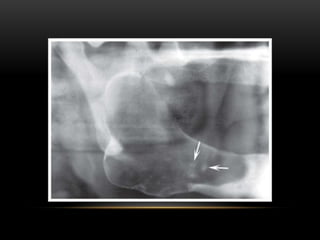

RADIOGRAPHIC FEATURES

This first develops at the arterial bifurcation as a result of increased

endothelial damage at these sites.

When calcification occurs,

these lesions may be visible on

the panoramic radiograph in

the soft tissues of the neck

adjacent to the greater cornu of

the hyoid bone and the cervical

vertebrae C3, C4 or the

intervertebral space between

them.

• The soft tissue calcifications are usually seen as

heterogeneous radiopacities with radiolucent voids,

which are multiple and irregular in shape, sharply

defined from the surrounding soft tissues and have a

vertical linear distribution